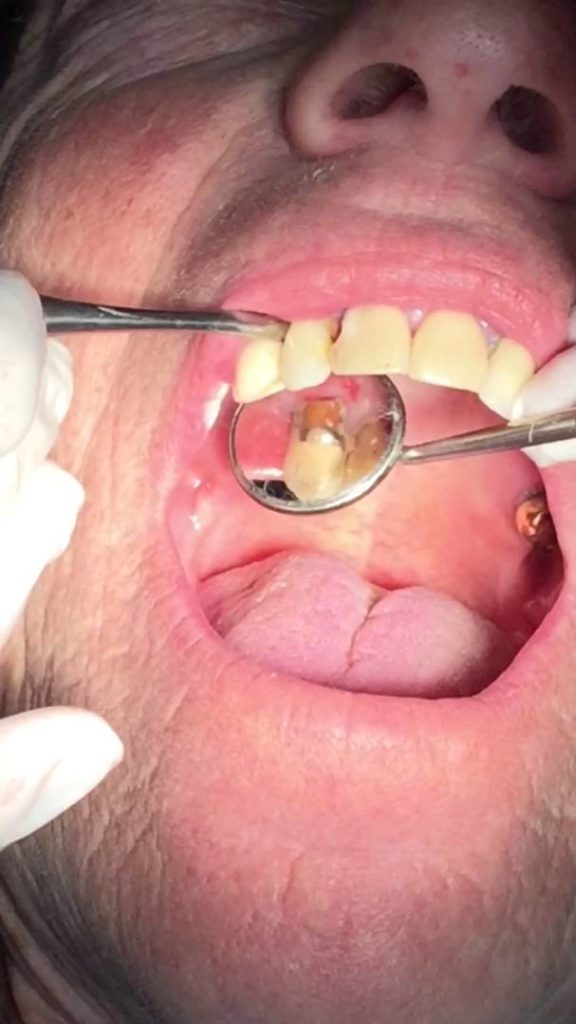

Palatal abscess curettage drainage of infected canine tooth – Dr Matt Tocuseanu @ Simi Dental Care